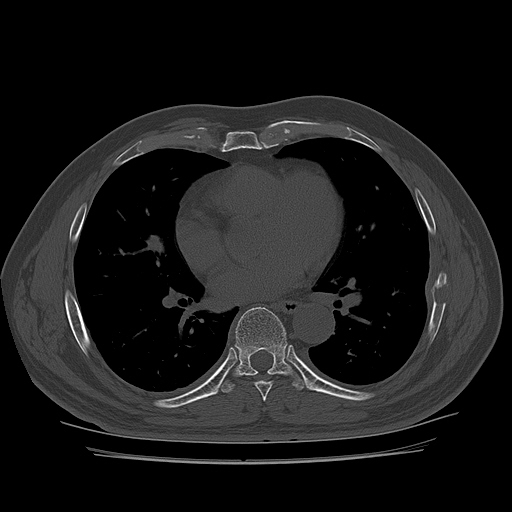

CT ; metastacic mass at rib and adjacent lung

CT image